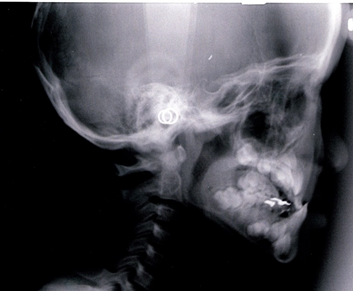

次に骨格で比べてみましょう。

同じ患者様の矯正治療終了後の骨格です。

不安定に見えていた咬み合わせが、反対咬合が改善されて安定して咬みあっていることが分かります。小学校低学年の治療であれば早期治療により反対咬合は容易に改善可能で、骨格の変化を考えてみても反対咬合は早期治療の効果が得られやすい症例と言えます。

次に骨格で比べて診ましょう。

7歳 初診時 女子の受け口の骨格

7歳 治療終了時 女子の受け口の骨格です。

同じ人の1年後の骨格です。

小学校低学年の治療であれば、この変化は普通に起こる変化です。

骨格のことからも受け口は早期治療の効果が得られやすい症例です。